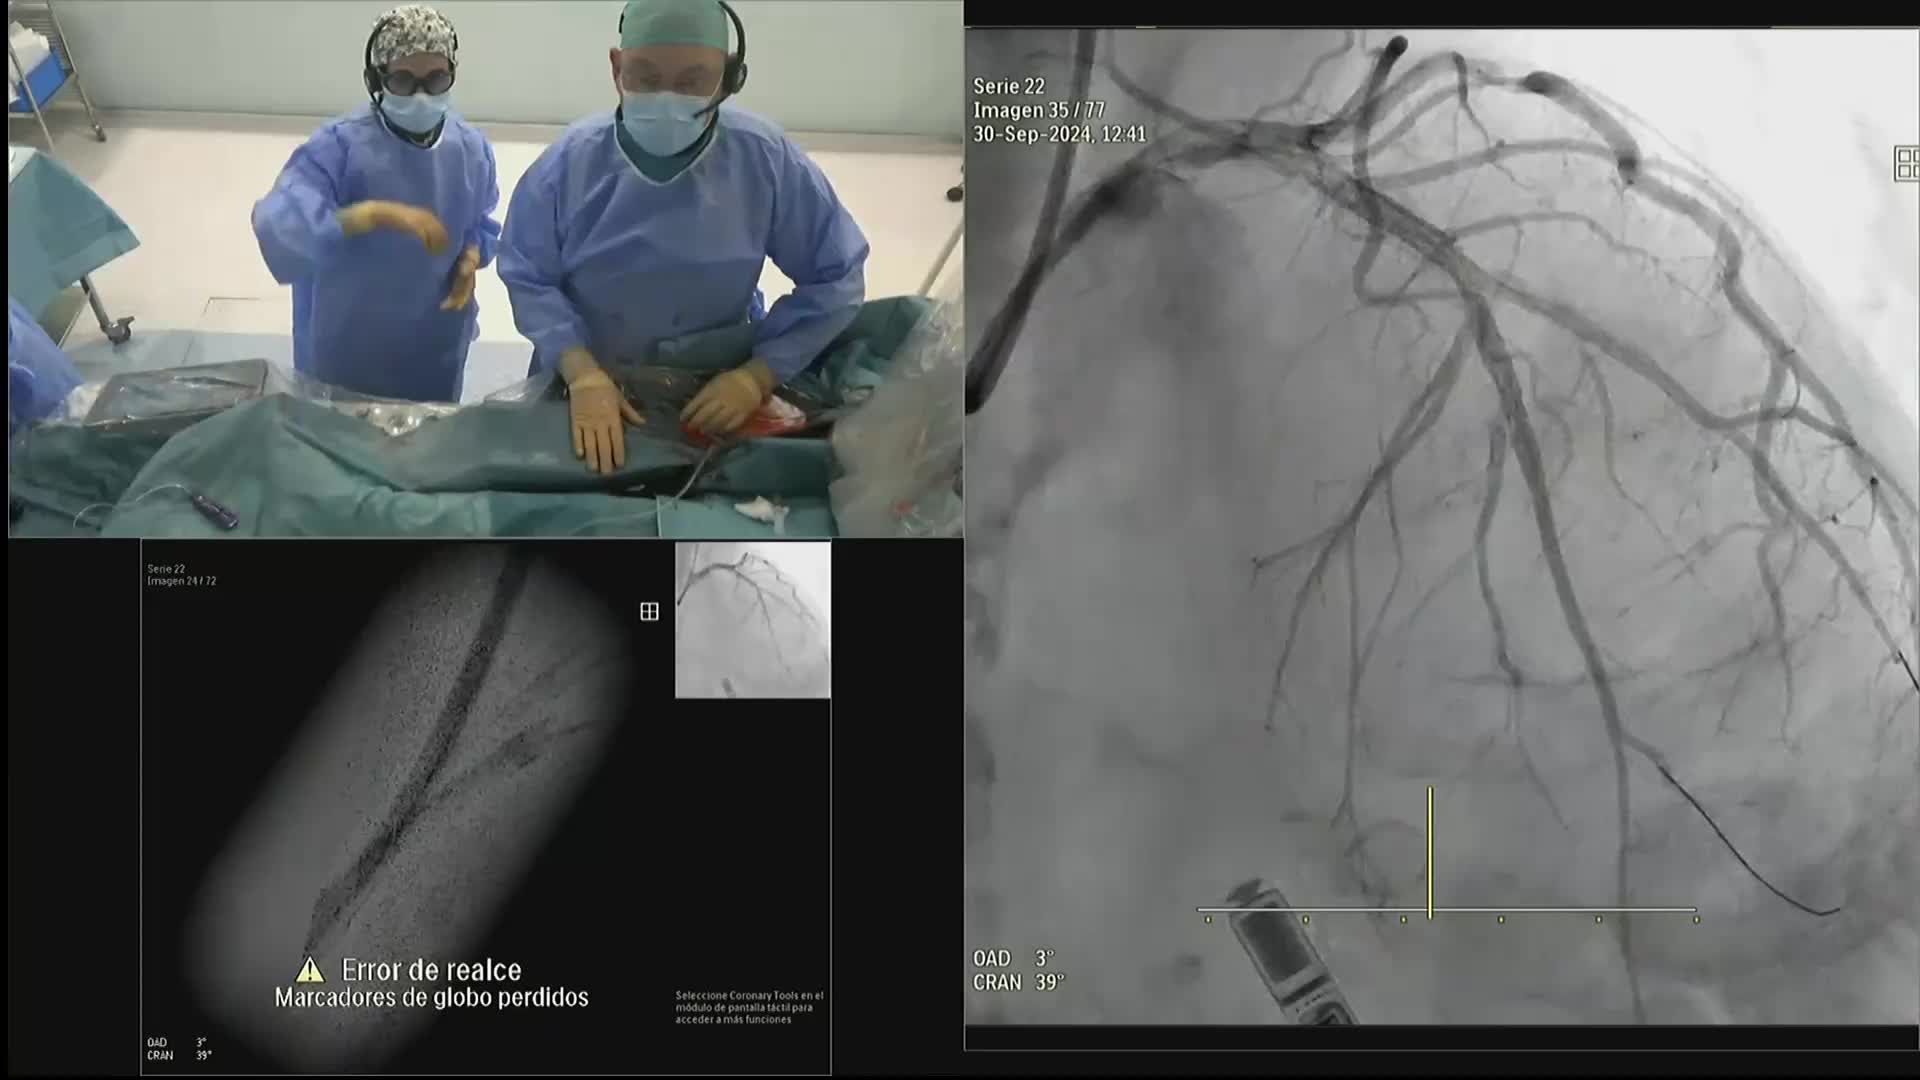

Ultralow Contrast PCI in complex and high risk patients - April 2024 Day One

Ultralow Contrast PCI in complex and high risk patients - April 2024 Day Two

Ultralow Contrast PCI in complex and high risk patients - November 2023 Day One

Ultralow Contrast PCI in complex and high risk patients - November 2023 Day Two

Ultralow Contrast PCI in complex and high risk patients - June 2023 Day One

Ultralow Contrast PCI in complex and high risk patients - June 2023 Day Two